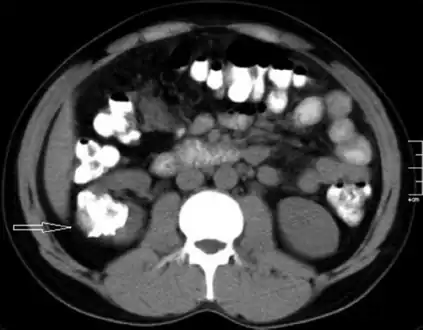

- Left flank pain and gross hematuria diagnosed with renal medullary fibroma

- Low mag.

- High mag.